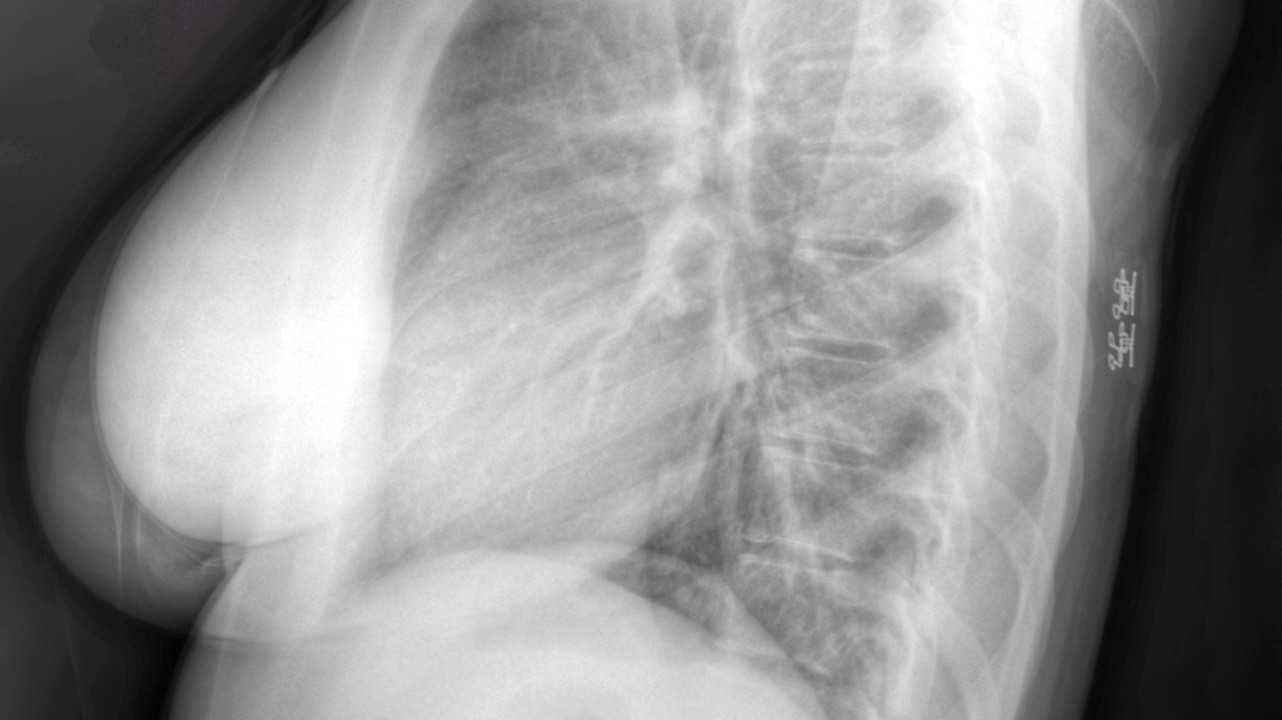

- Ангиомиолипома, состоящая из аномально разросшихся сосудов и жировой ткани. Чаще всего ее обнаруживают в поясничном или грудном отделах позвоночника. Как правило, возникает в теле одного позвонка и может проявляться болью в спине, так как уменьшает высоту позвонка и приводит к сдавливанию нервных корешков. Образование обычно выявляют случайно у людей в возрасте 30-40 лет. При сильной компрессии, т.е. при сдавливании нервных структур, проводят лечение – пункционную вертебропластику (“цементирование” позвонка). Иногда ангиомиолипому обнаруживают в почке. При небольших размерах (до 1,0-1,5 см) лечения не требует, за образованием наблюдают, периодически выполняя ультразвуковое исследование.